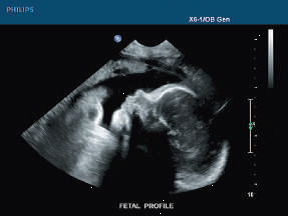

- Biologic Effects of Ultrasound in Healthcare Setting The instrument performing the emission of the sound waves and the recording of their bouncing back is referred to as the transducer and the medical practitioner generally gently presses the transducer against the skin of […]

- Ultrasound Scanning: Diagnosing Health Conditions The calculation is based on the time taken by the wave to return by measuring the distance, mass, nature, and stability of the object hit.